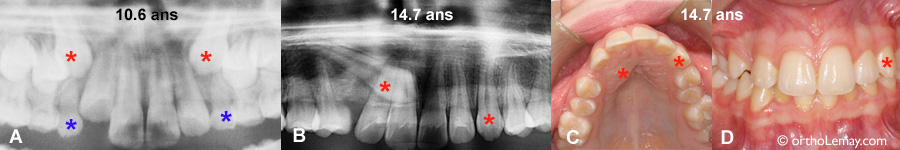

Extractions sélectives pour influencer la direction d’éruption des canines permanentes

Extractions sélectives pour influencer la direction d’éruption des canines permanentes. (A) À 10.6 ans, ce garçon présentait des canines (* rouges) inclinées vers les racines des latérales mais dans une “zone” favorable pour influencer leur éruption à l’aide d’extractions sélectives. Les canines temporaires et la dent adjacente (première molaire temporaire) furent extraites. (B) Un an plus tard, la direction d’éruption des canines s’est améliorée et est devenue plus droite et verticale, malgré un manque d’espace toujours présent.